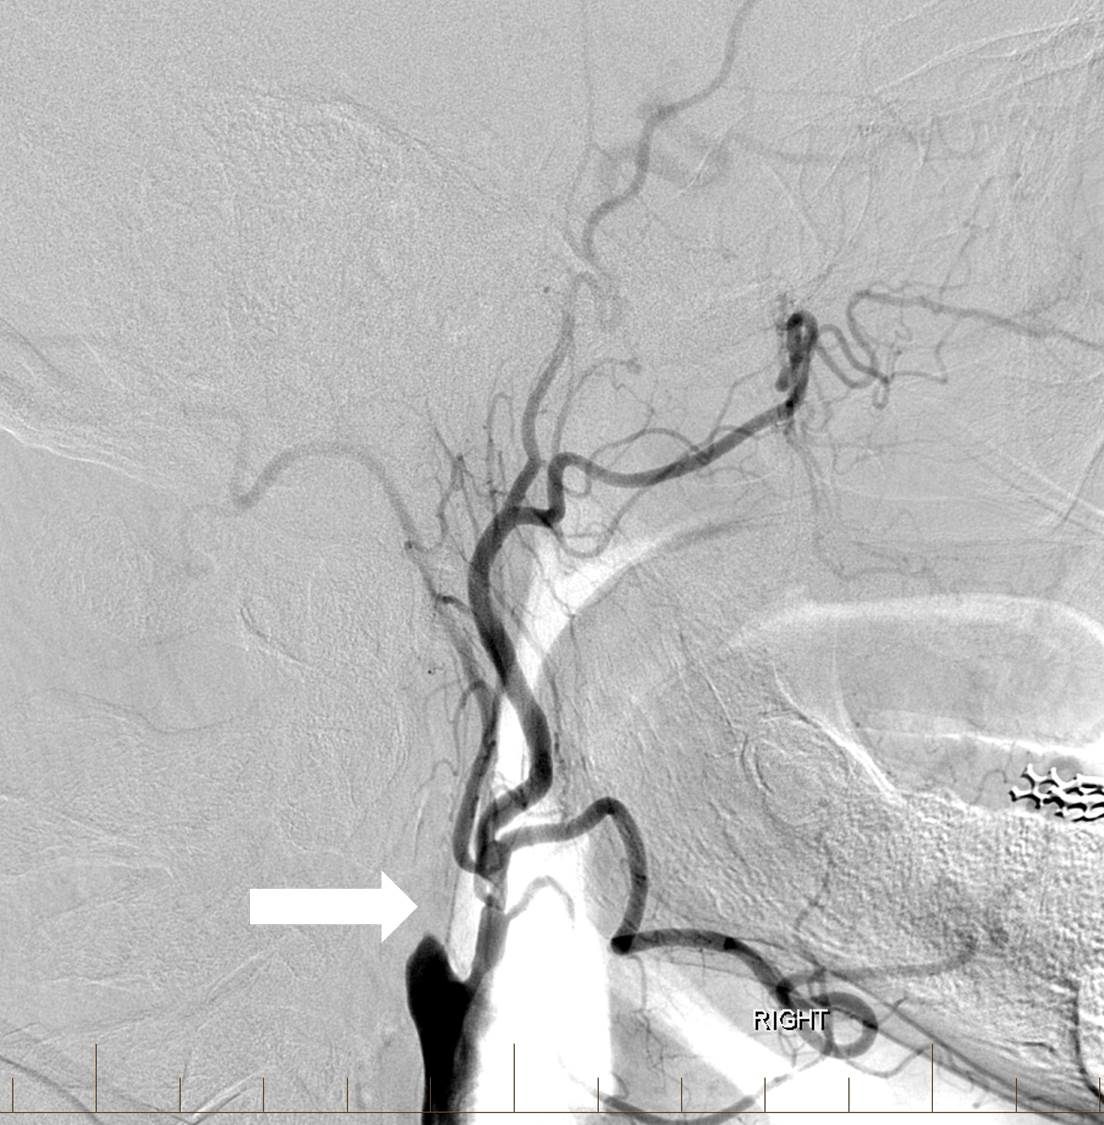

tPA was administered intravenously, and the patient was transferred to the interventional neuroradiology suite. Biplane digital subtraction angiography revealed a complete occlusion of the cervical right ICA at the vessel’s origin due to extensive atherosclerotic disease (Figure 6).